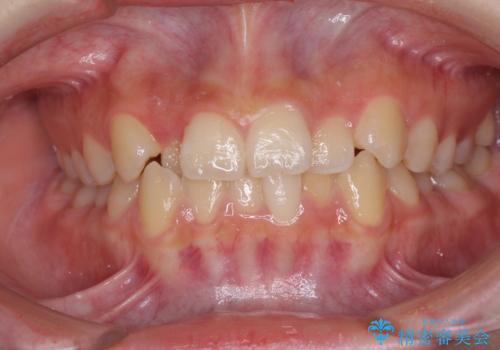

前歯のガタガタ 治療期間がかかっても良いので非抜歯でマウスピースで

前歯のがたつき インビザラインで抜歯矯正